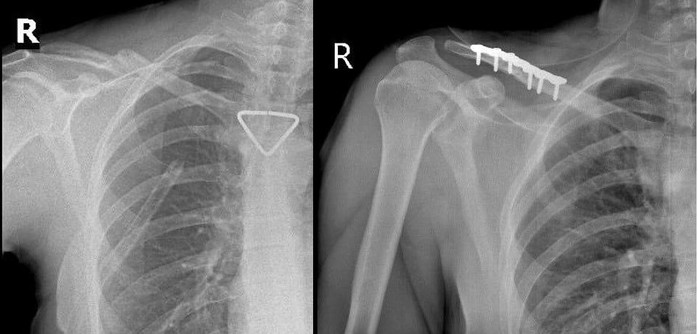

Qua hội chẩn liên chuyên khoa và đánh giá của bác sĩ gây mê hồi sức, người bệnh đủ điều kiện an toàn để thực hiện phẫu thuật kết hợp xương đòn phải bằng nẹp vít. Ca mổ do ê-kíp BSCKII Trần Văn Dương và BS Phạm Ngọc Huy thực hiện, diễn ra thuận lợi. Nẹp vít được đặt vững chắc, trục xương phục hồi giải phẫu tốt.

Hình ảnh Xquang trước và sau mổ. Nẹp vít được đặt vững chắc, trục xương phục hồi giải phẫu tốt